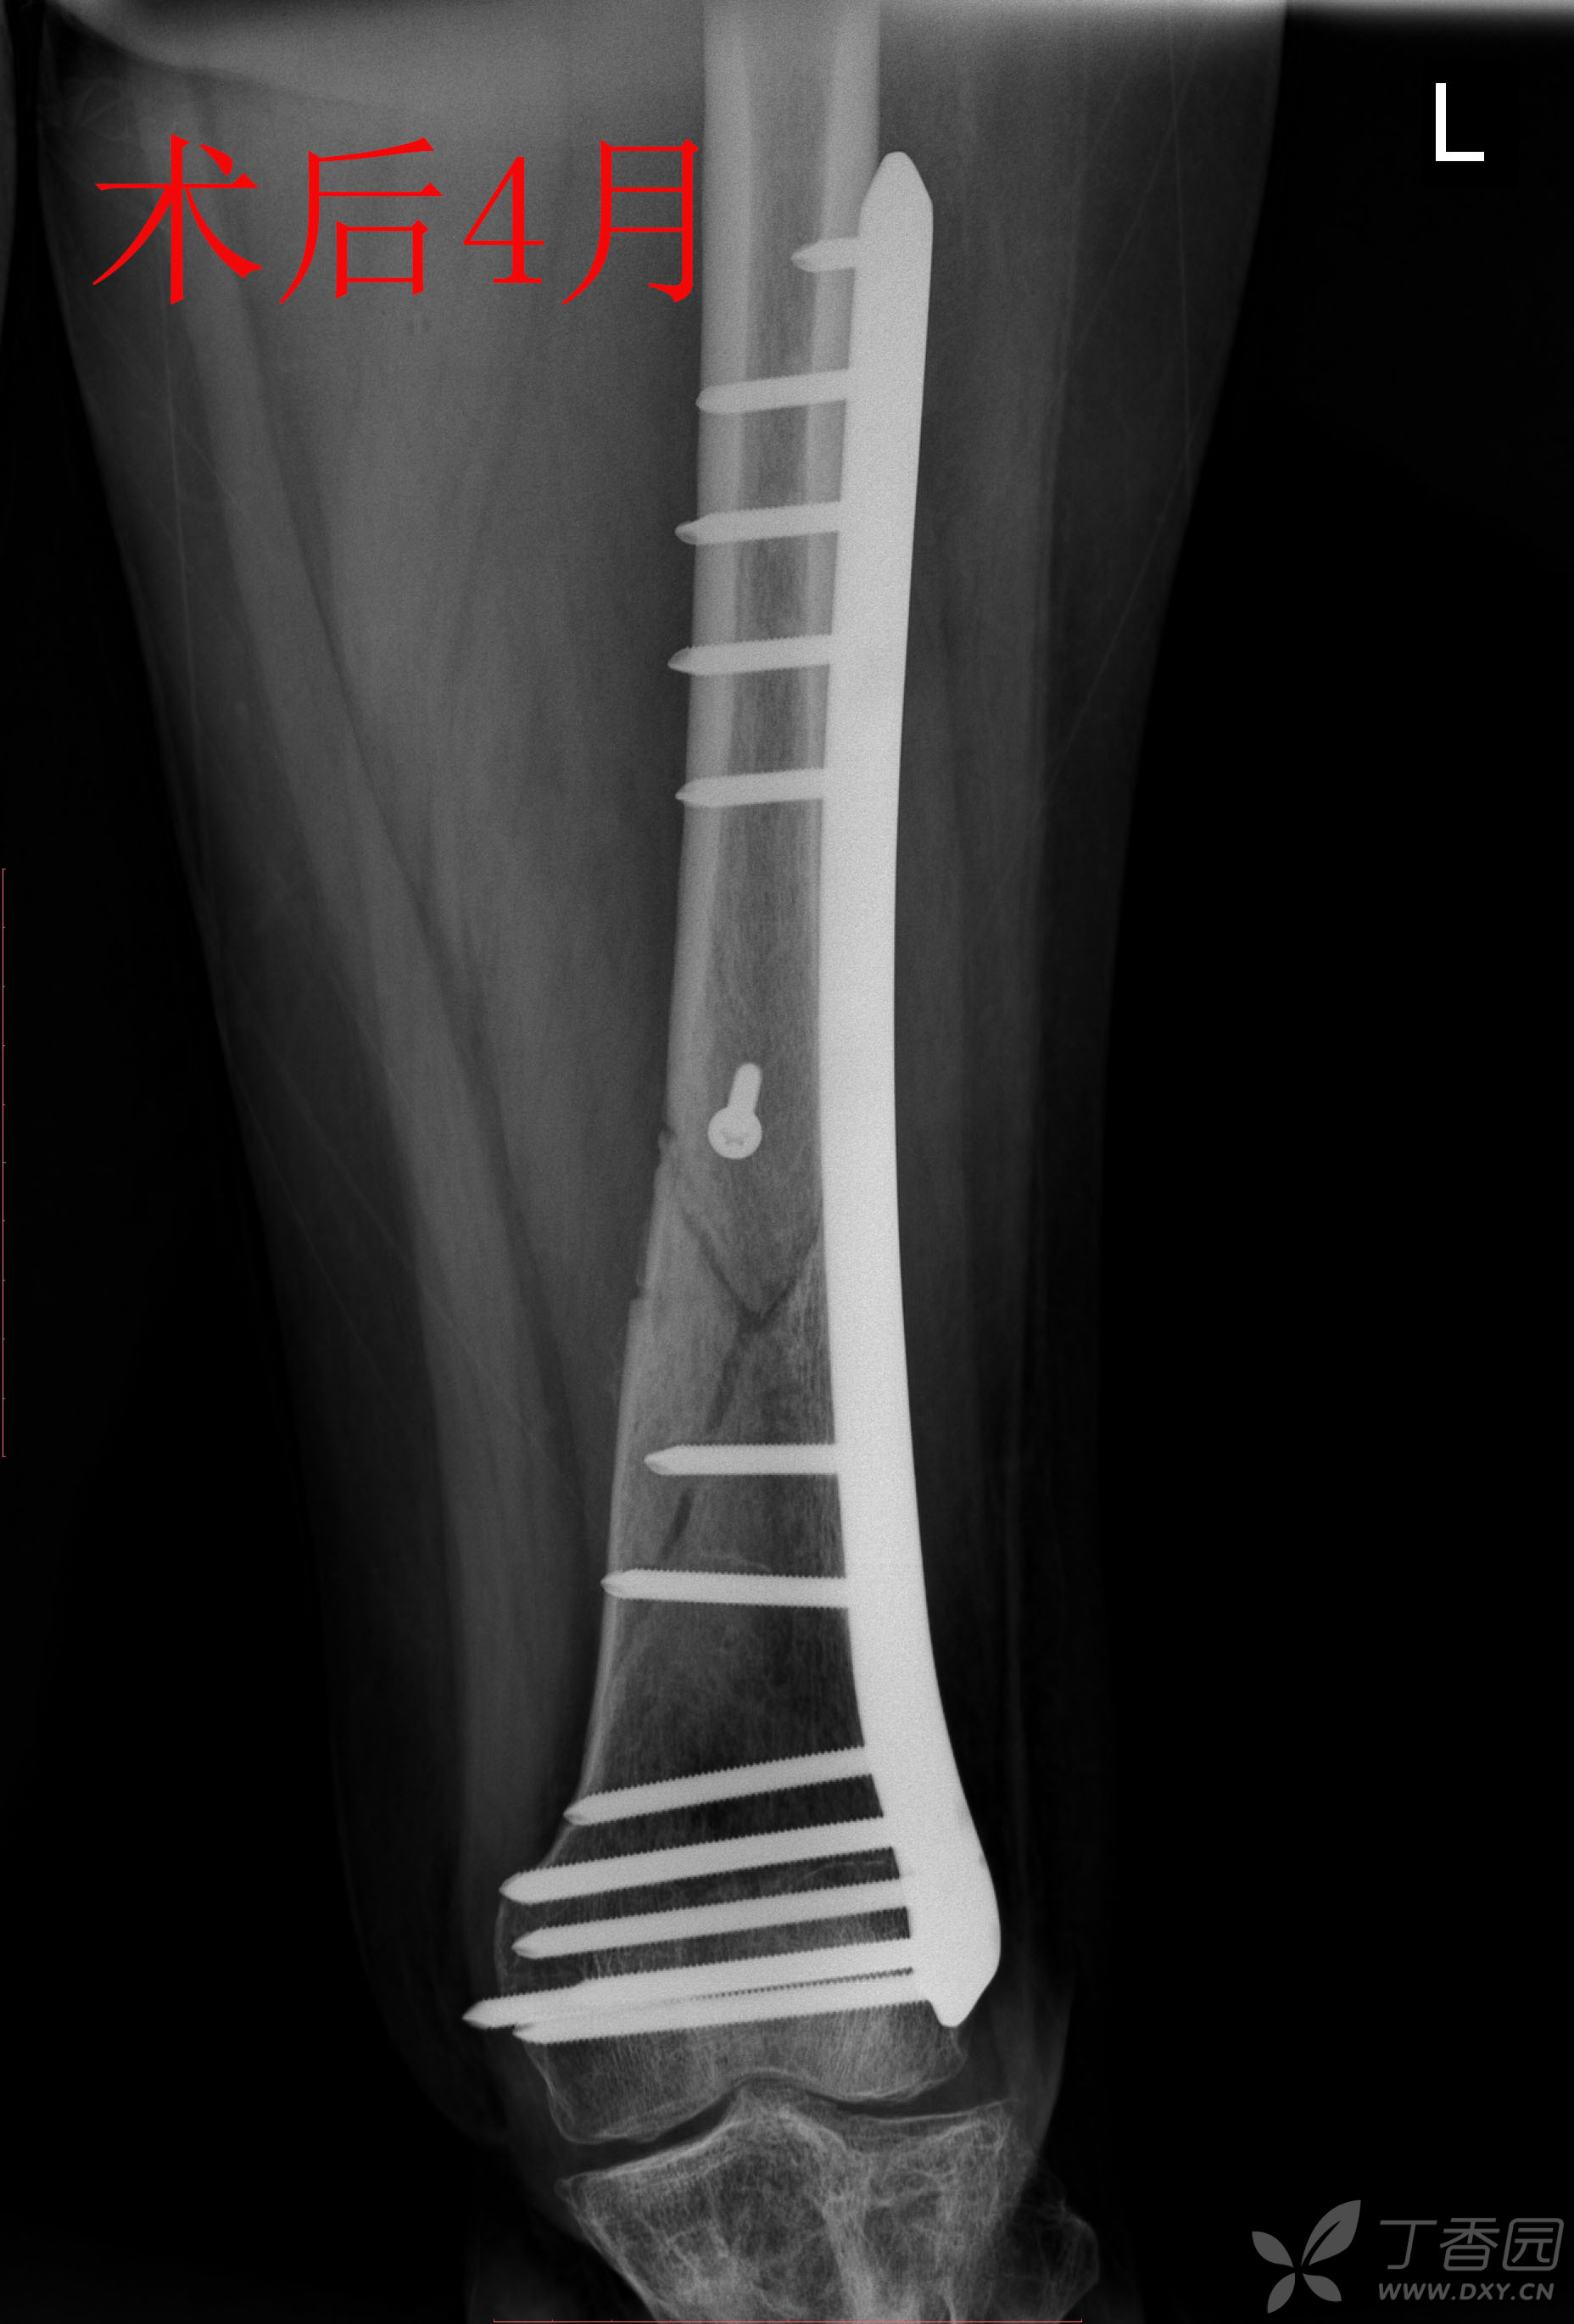

胫腓骨骨折 骨科专业讨论版 丁香园论坛

股骨远端骨折锁定钢板固定术后14月骨不连 影像资料清晰 连贯 请老师们多指点 骨科专业讨论版 丁香园论坛